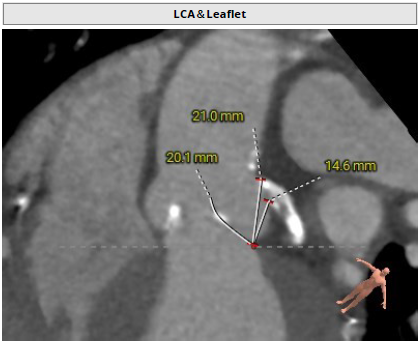

主动脉根部评估

瓣环周长83.2mm,周长径26.5mm

LVOT周长 92.5mm,周长径29.5mm

SOV 31.7mm*35.2mm*37.9mm

STJ 周长径32.7mm

升主动脉周长径38.1mm

瓣环水平夹角60°

左冠开口高度14.6mm